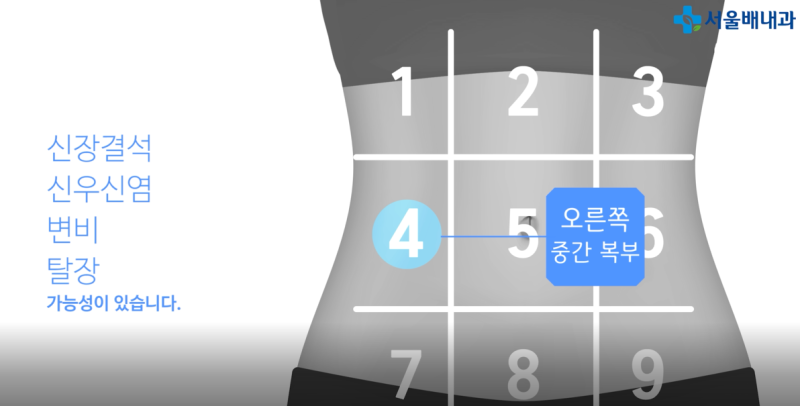

적어도 일주일에 한 번 정도는 염증 치료를 받으러 방문할 수 있지만, 그 과정에서 왼쪽 태반 밑에 남은 통증은 결국 관리가 필요해 비용과 시간 모두 비효율적으로 보였습니다.두통증은 왼쪽 태양과 관절염 등 심근통증으로 인한 근육 통증, 통증, 통증, 통증, 통증, 통증, 통증 등 근육 통증을 유발한다.그래서 저는 결심했습니다.나는 그것을 시도해봤어요.위 아래 통증에 직접 사용한 사용 후기사실, 초기 비용은 조금 높았지만, 제가 계속 사용하고 있다고 가정하는 것보다 훨씬 효율적이었습니다.제가 그것을 받았고, 우리가 예상했던 것보다 더 빨리 고통받는 지역보다 빨리 보살핌을 받았습니다.배가 위쪽에 있는 배가 아파요. 배가 위쪽에 통증을 호소했지만, 위쪽에 있는 근육에 통증이 심해졌다.나는 솔직히 즉각 반응을 보였다.사실 초기 비용은 조금 비쌌지만, 계속 사용한다고 가정하면 직접 가지러 가는 것보다 효율적이었습니다.제가 받아서 사용했는데, 생각보다 아픈 부위를 빨리 치료해 주었습니다.위의 오른쪽 구덩이의 통증 > 왼쪽 구덩이의 통증 > 위의 구덩이 아래의 통증 순서대로 아팠지만, 위의 구덩이 주위를 모두 사용한 후에는 안쪽에서 근육이 당기는 느낌이 사라졌습니다.저는 솔직히 즉각적인 반응에 놀랐습니다.이 방법은 오래전부터 전류를 통한 통증 관리의 일환으로 여러 기관에서 널리 사용되고 있어 집에서도 안심하고 사용하실 수 있습니다!한국에서 개발된 리무버인 줄 알았는데 아니었어요.유럽인들이 갑자기 고통을 준비하기 때문에 디럭스 스토리를 준비하기 어렵다.오른쪽 피치 통증을 위해 사용하면서 근육은 근육이 약간 느슨하게 느껴졌고, 근육이 약간 느슨하게 느껴졌다.전기가 있으면 안 아파요. 하지만 오른쪽 시원한 느낌은 기분이 좋을 것 같아요.높은 휴대성과 편리함으로 사용하기 좋습니다또 다른 장점은 일상 생활에서 운반할 수 있다는 것입니다.갑자기, 통증이 심해지고 숨을 쉴 때, 특히 숨을 들이고 숨을 쉴 때렸다.그리고 무의식적으로 이 자세를 취해서 고통을 느꼈을 때 내 일에 집중하기 힘들었다.하지만, 통증이 갑자기 올라가면, 내 옷을 벗기고, 옷 위에 올려서 호흡이 더 빨리 통증이 심해지고, 진통제가 더 빨리 치료하기가 더 빨라졌다.일상생활에서 휴대할 수 있고 원할 때 언제든지 사용할 수 있다는 점도 장점으로 꼽혔습니다.특히 몸을 뒤로 젖히거나 숨을 크게 쉴 때 갑자기 따끔거리고 통증이 느껴졌습니다.그리고 무의식적으로 이런 자세를 취하며 고통을 느낄 때, 잠시 지속되었기 때문에 일에 집중하기가 어려웠습니다.하지만 지금은 갑자기 통증이 높아지면 기기를 꺼내 옷에 붙이고 클릭하면 숨막히는 통증이 금방 진정되기 때문에 진통제를 먹는 것보다 훨씬 빨리 치료하는 것이 좋았습니다.오른쪽 태음순의 통증과 태음순 아래의 통증 외에도, 여러분은 피부와 근육이 위치한 곳이라면 어디서든 사용할 수 있습니다!저는 기계의 지원을 받아 그것을 썼습니다.